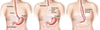

Qual a principal causa de acalásia?

Qual seu mecanismo fisiopatológico?

IDIOPÁTICA

Destruição do plexo mioentérico de AUERBACH

Acaláisa → Auerbach

Qual a principal causa secundária de acalásia?

Qual seu mecanismo?

DOENÇA DE CHAGAS

Destruição do plexo mioentérico (Auerbach) e Submucoso (Meissner)

Quais as manifestações clínicas da Acalásia?

- Disfagia

- Regurgitação

- Perda de peso

- Broncoaspiração

- Halitose

Como diferenciar a clínica da Acalásia de uma Neoplasia de Esôfago?

- NEO: Paciente mais idoso (70 anos), quadro de evolução mais rápida (1 ano), perda de peso mais intensa

- ACALÁSIA: Paciente um pouco mais jovem, evolução arrastada (10-15 anos)

Qual o primeiro exame na suspeita de acalásia?

ESOFAGOGRAFIA BARITADA

Qual o nome deste sinal?

SINAL DO BICO DE PÁSSARO / CHAMA DE VELA